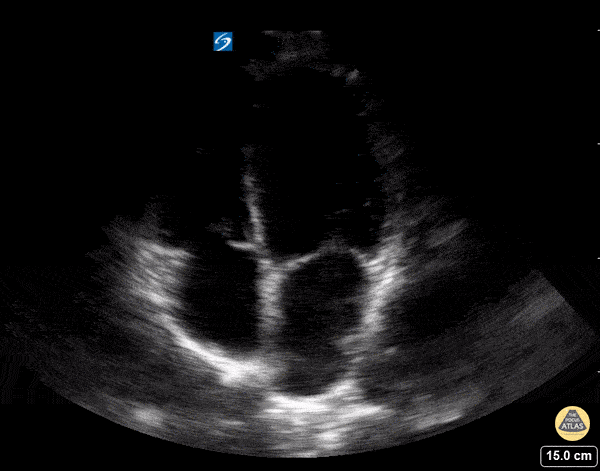

Normal Cardiac Anatomy - Apical Four Chamber - Normal

In this view we are able to visualize all four chambers of the heart. Clockwise from the top left of the screen we see the right ventricle, left ventricle, left atrium, and right atrium. We can also see the tricuspid valve between the RA and RV and the mitral valve between the LA and LV. Hannah Kopinski - MS4, Dr. Lindsay Davis - NYU/Bellevue Department of Emergency Ultrasound